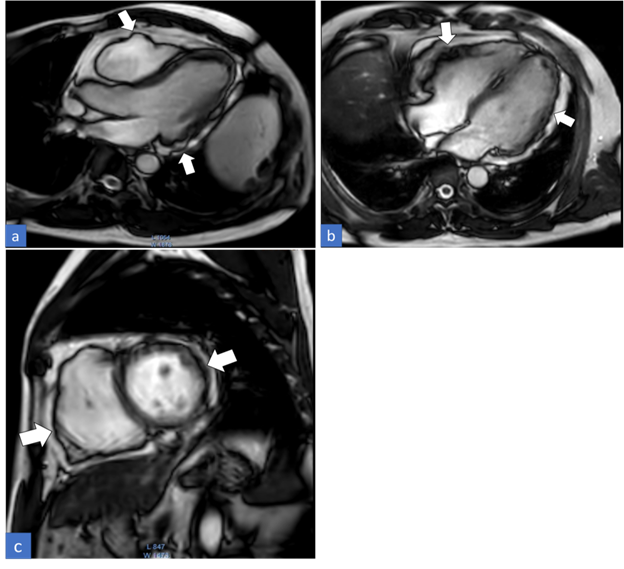

Cardiac MRI with contrast was performed for the patient on a 3Tesla platform. The CMR sequences of transverse black/bright blood images, vertical long axis, four-chamber, and short-axis cine images, left ventricular outflow tract (LVOT), right ventricular outflow tract (RVOT) views along with three-chamber cine images, and early plus delayed gadolinium enhancement sequences were obtained. The imaging findings showed dilated right atrium, right ventricle, and RVOT with irregularity of both ventricular wall (predominantly on the right side) (Figure 1). The right ventricular wall was noted to have increased trabeculations with dyssynchronous motion of the wall. Indexed end diastolic volume of the right ventricle was 120cc and the right ventricular ejection fraction (RVEF) was measured to be 32%. The delayed gadolinium images depicted diffuse enhancement in the right ventricular wall and RVOT. Patchy mid myocardial enhancement was also noted in the left ventricular wall involving the lateral segments in the basal and mid cavities (Figure 2). Mild tricuspid regurgitation with a regurgitant fraction of 16% was also noted. Based on the CMR findings and features satisfying modified task force criteria, diagnosis of ARVC with biventricular involvement was made.

ARVC is an inherited form of cardiomyopathy mostly seen in young adults that frequently goes undiagnosed as its clinical signs and symptoms vary from being completely symptomless to fatal arrhythmia and sudden mortality.2 Hence, to make the interpretation easier, the diagnostic criteria namely “The task force criteria” were first introduced in 1994. It has been followed thereafter with a major update in 2010. The significant CMR imaging findings included in the criteria are Regional RV akinesia or dyskinesia or dyssynchronous RV contraction plus one of the following: RV end-diastolic volume indexes ≥ 110 mL/m2 (male) or ≥ 100 mL/m2 (female) Or RV ejection fraction ≤ 40% (1, 2, 3). Our present case here met all of the mentioned CMR imaging criteria, thus giving a confirmed diagnosis of ARVC. As the name implies, ARVC primarily affects the right ventricle, however, it can also affect the left ventricle.4,5 This is when CMR is again considered a crucial modality to assess the left ventricular involvement as it may not be evident on an echocardiogram. In our case as well CMR revealed the involvement of the left ventricle giving an impression of an “Arrhythmogenic Biventricular Cardiomyopathy” rather.